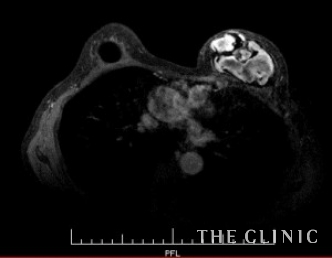

エコーではカプセルが厚く、内部が描出されないためMRI検査を行いました。

MRI画像です。

左はバッグの内部に高信号領域を認めました。